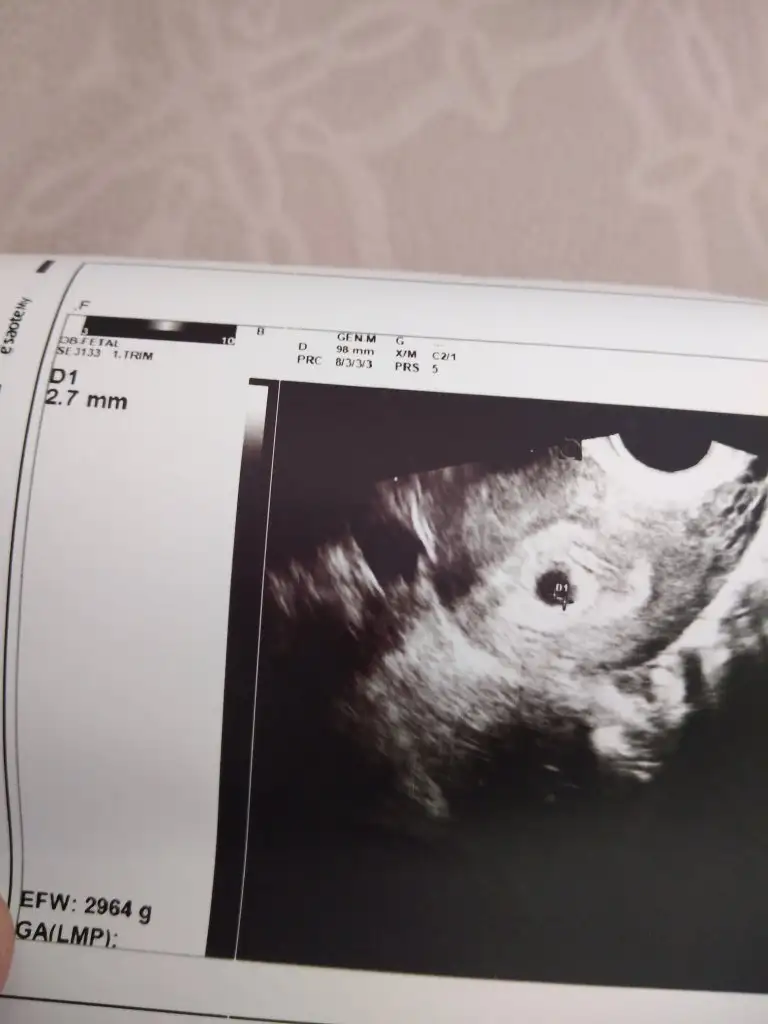

Kızlar ben kontrolden geldim karından baktılar hem bebeği hem kalp atışını gördüler ama doktor çok emin olamadı kalp atışından bide vajinal bakmak istedi vajinal bakınca daha net bir şekilde kalp atışı var dedi çok şükür cihazları zayıf olduğundan sanırım biraz görüntü kalitesi de zatıf ama paylaşayım

Eklentiler

• 16623794040316192399409149797268.webp

20,2 KB · Görüntüleme: 75

6+3 ile uyumlu dedi canım bidaha 12. Haftaya çağırdı ama ben başka hastaneye gidicem 10. Haftada